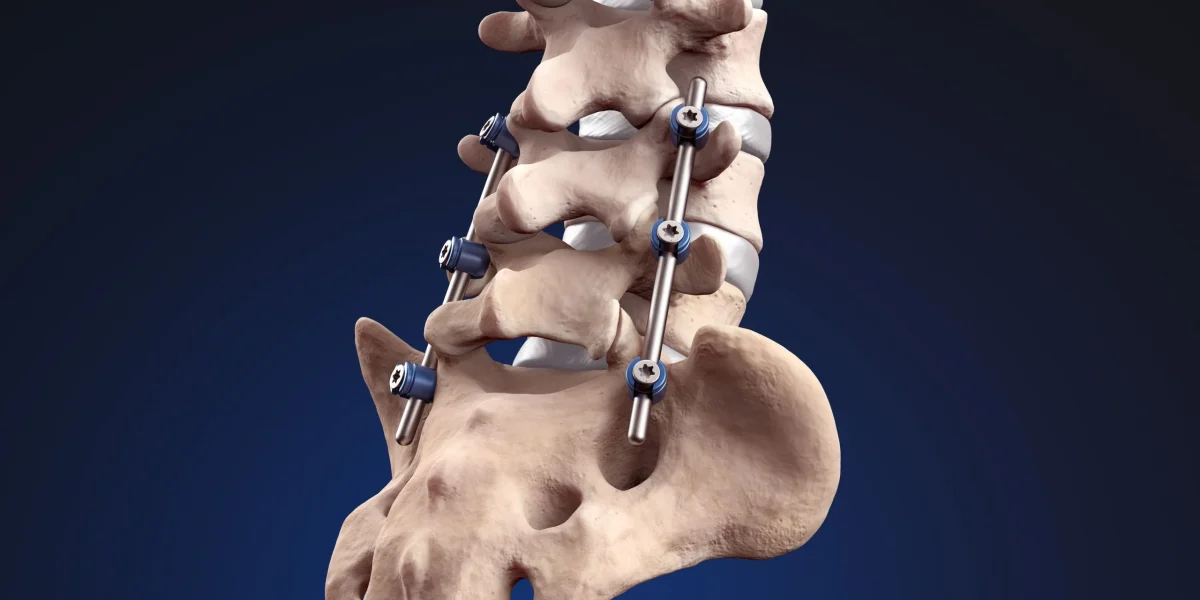

Spinal fusion surgery is a traditional approach to treating conditions such as herniated discs, sciatica, degenerative disc disease, and spinal stenosis. During this procedure, two or more vertebrae are permanently joined using metal hardware (screws, rods, and cages) along with bone grafts. The goal is to eliminate motion at a painful segment of the spine.

During a spinal fusion procedure, surgeons access the spine through various approaches. They remove the damaged disc material, prepare the vertebral surfaces, place bone graft material between the vertebrae, and secure everything with metal hardware to hold the vertebrae in position while the bone graft heals and forms a solid bony bridge.

The fusion process takes approximately 3–6 months, during which the vertebrae gradually grow together. Once complete, these vertebrae function as a single, solid bone segment, permanently eliminating motion at that level.

Once fused, the vertebrae no longer move independently. This loss of natural motion can limit flexibility and affect posture and overall biomechanics. The spine is designed to move, and eliminating motion at one segment places additional stress on the remaining mobile segments.

Why This Happens

Fusion transfers stress to the spinal levels above and below the fused area, leading to accelerated degeneration. The spine functions as an interconnected chain of motion segments. When one segment is locked in place, the segments around it must compensate by moving more than they were designed to. This excessive motion accelerates wear and tear, causing disc degeneration, facet joint arthritis, and eventually new pain.